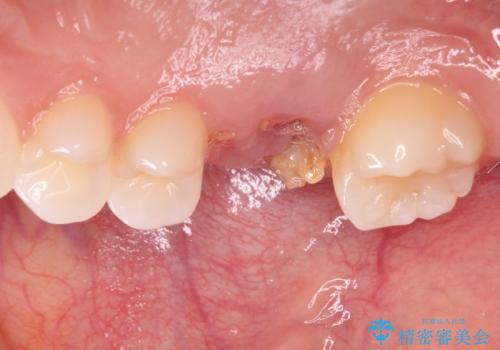

- 歯がほとんどなくなってしまうまで虫歯を放置してしまったとのことで来院された患者様です。

抜歯が必要であることは患者様自身も理解されており、インプラントによる欠損補綴治療を希望されていらっしゃいました。

抜歯前のCTにより、インプラントを埋入するために必要な歯槽骨量が不足することが予想されたため、サイナスソケットリフトにより上顎洞内の粘膜を挙上して、インプラントを埋入することとしました。

虫歯を放置した期間が長かったため、対合の下顎大臼歯が上顎に迫ってきており、咬み合わせは非常にシビアでした。